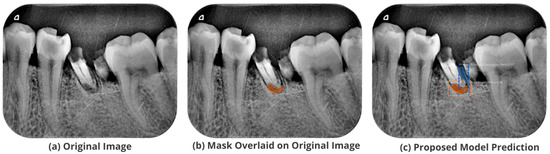

3.5. Comparison with Test Images

The proposed model accurately predicts and localizes the lesions as depicted in Figure 10, Figure 11, Figure 12, Figure 13 and Figure 14. The results indicate that the model makes predictions similar to that of the annotated masks using the periapical radiographic images. Additionally, the proposed model was evaluated based on performance indicators like precision, recall, F1 score, and accuracy for each classified periodontal lesion. The obtained results indicate that the proposed backbone network provides good performance for disease classification. All the test images for the proposed study show a 95% confidence level indicating that the database annotations are in the right direction.

Figure 10.

Test performance for the localization of a ’Primary Endo and Secondary Perio’ lesion.